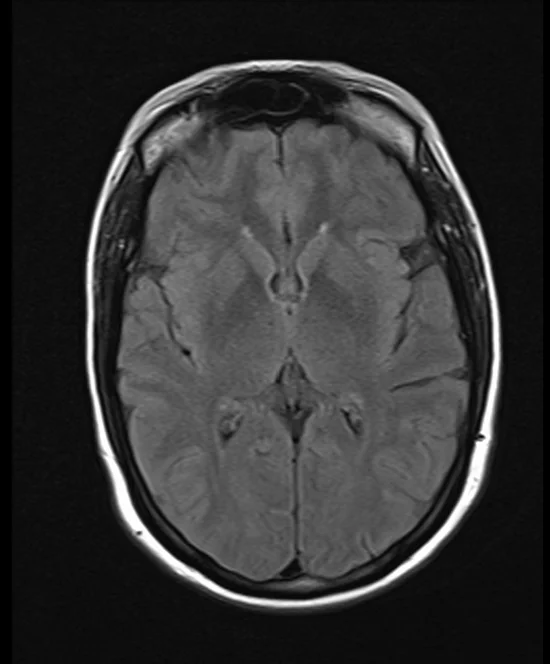

brain mri t2 flair axial images